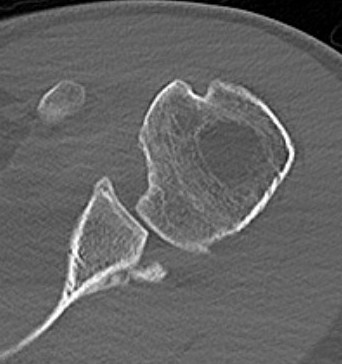

CT scan

Confirms dislocation

Reverse Hill Sachs

Humeral head defect

- caused by impaction of anterior humeral head on posterior glenoid

- intra-articular

- measured as a percentage of the articular surface